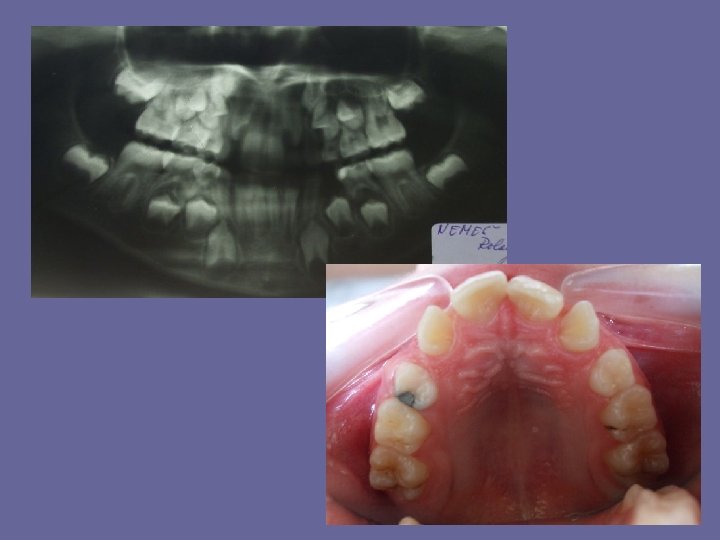

REPLACEMENT OF INCISORS • if there is not sufficient growth in arch width the lateral incisors may be trapped in their palatal position. • When the upper incisors erupt they are frequently distally inclined, there is a median diastema. This is due to the incisor roots being crowded mesially by the permanent canine crowns and should not be mistaken for a malocclusion. When the permanent canines erupt the median diastema will usually close.

REPLACEMENT OF INCISORS • When the lower incisors erupt they are often crowded but it is improve by further growth in arch width. • If the deciduous incisor root is not resorbed normally, the permanent incisor may be deflected lingually or palatally.

REPLACEMENT OF INCISORS The lower incisors erupt before the uppers. It causes the accelerated growth of mandible and the “ 2 th physiological reduction of overbite”.